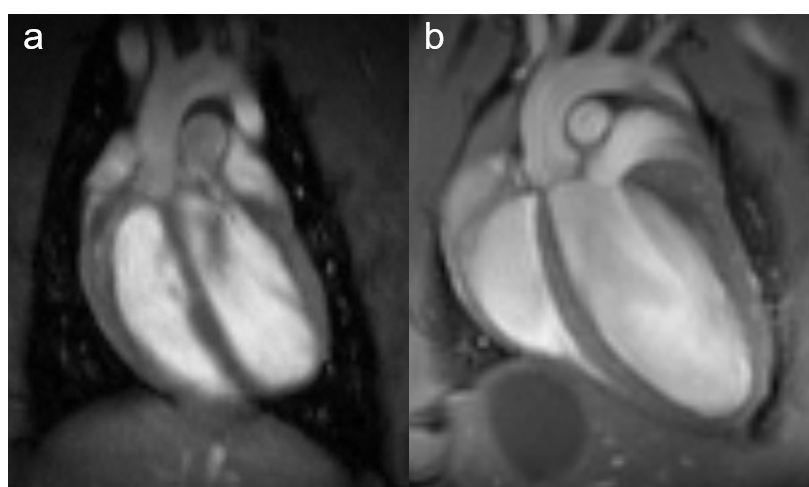

Fig. 1: Rat and mouse heart MRI. 4-chamber-views of a rat (a), upper panel and mouse heart (b), lower panel are displayed. Beside the lumen of the left and right chamber, the left and right atria, the myocardium and the up-going vessels are visible. For rat a 72 mm volume transmit-only together with 20 mm recieve-only planar surface coil, both room temperature, and for mouse the 72 mm volume transmit-only and the cryogenic 4 element 1H array receive-only coil were used. Intragate Flash (Fast Low Angle Shot) sequence for rat (repetition time: 6.2 ms; echo time: 1.3 ms; oversampling:150; flip angle: 10 deg; slice thickness: 1.0 mm; FOV: 45x45 mm and matrix: 128x128 .Intragate UTE (Ultra Short Echo Time) for mouse: repetition time: 8.0 ms; echo time: 0.36 ms; oversampling: 100; flip angle: 15 deg; slice thickness: 1.0 mm; FOV: 22x22 mm and matrix: 128x128.

MRI is a well-established modality for imaging of the cardiovascular system in rat and mice. Beside determination of tissue, organ or tumor sizes, our main focus lies on monitoring changes over time after treatment of transgenic mice. One of the best-known forms of dynamic MRI experiments is the functional MRI, typically monitoring changes in blood flow. In the recent years MRI has become the standard for the quantitative evaluation of cardiac function, masses, and infarct size. Wall motion and strain analysis are used to display myocardial dysfunction. To obtain information on the morphology and functional parameters of rat and transgenic mice heart, we established standard protocols that enable us to rapidly acquire high quality images.